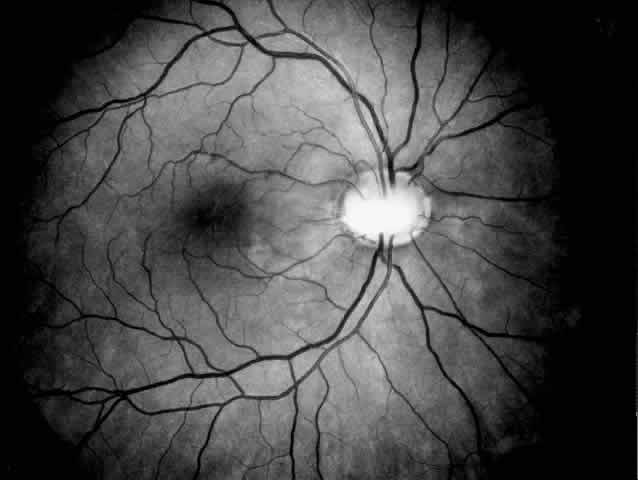

Alport's syndrome may affect the cornea, lens, and retina, the most characteristic ocular signs being posterior polymorphous dystrophy, anterior lenticonus, and superficial perimacular flecks (Fig. 4). There is growing evidence that the ocular abnormalities, like the glomerular lesions, result from a common defect in basement membrane formation.56,58,59 Changes are uncommon and subtle in young patients with Alport's syndrome and seem to increase in frequency and severity with age.60 The corneal changes associated with Alport's syndrome include endothelial vesicles compatible with posterior polymorphous dystrophy, subepithelial opacities,58 corneal arcus, and recurrent corneal epithelial erosions.

Fig. 4. Superficial perimacular flecks in a 15-year-old boy with normal vision. Alport's nephritis was diagnosed at the age of 3 years and progressed to end-stage renal disease at the age of 14 years. Perceptive high-tone hearing loss was detected at the age of 11 years. The proband's mother has had persistent microscopic hematuria since the age of 20 years but had no other manifestations of the disease.

Superficial perimacular flecks do not interfere with vision but are a reliable indicator of Alport's syndrome and are often associated with renal deterioration.55,56,60 Midperipheral retinal flecks and pigment epithelial lesions are also specific for Alport's syndrome. Macular pigmentation and weakened foveal reflex have been observed occasionally, and there have been individual reports of macular hole, retinal detachment, and optic disc drusen in patients with Alport's syndrome. Electrophysiologic abnormalities are unusual in classic Alport's syndrome. Retinitis pigmentosa and cone dystrophy, however, have been described in a few families with hereditary nephritis.